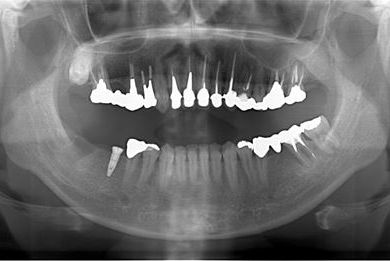

インプラントの症例写真 IMPLANT

インプラント治療

| 性別/年齢 | 女性 / 34歳 | ||||||||||||||||||||||||||||||||

| 主訴 | 左上奥の歯茎の腫れと、口臭などが気になっています。 | ||||||||||||||||||||||||||||||||

| 治療方針 | 右下奥欠損部分をインプラント治療にて機能的・審美的回復を行う。 | ||||||||||||||||||||||||||||||||

| 治療内容 | インプラント1本、メタルボンドセラミッククラウン1本 | ||||||||||||||||||||||||||||||||

| 総治療費 | 252,000円 | ||||||||||||||||||||||||||||||||

| 治療期間 | 4ヶ月 |